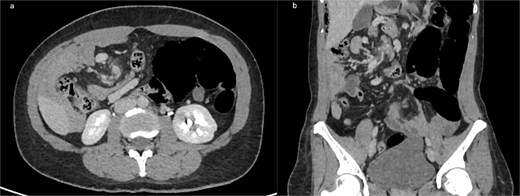

Axial (a) and coronal (b) contrast-enhanced CT images demonstrating intestinal malrotation, characterized by right-sided small bowel loops and left-sided colonic segments, with an abnormal relationship between the SMA and vein.